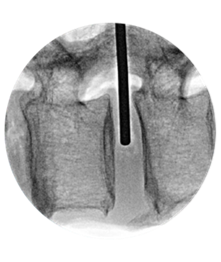

MEASURE

TRIAL

IMPLANT